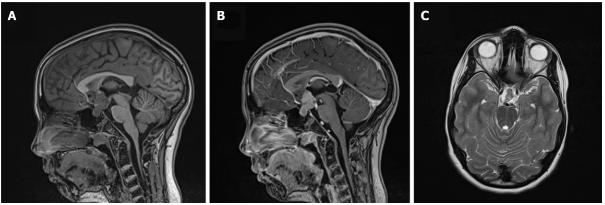

脑部紧急核磁共振成像(MRI)显示鞍上肿块尺寸为22mm×18mm,肿瘤压迫前连合和灰结节,延伸至第三脑室底部。病灶在非增强T1加权像(WI)上与大脑信号相同,显示均匀增强。轴向T2WI MRI扫描显示病变与大脑信号相同。漏斗部和视交叉合并到肿块中,在松果体区发现一个13mm×10mm的囊肿。未观察到钙化、缺血或出血迹象(图1)。

图1、十二岁女孩的鞍上生殖细胞瘤。 矢状位脑磁共振成像(MRI)扫描显示一个具有小叶轮廓的鞍上病变,邻近灰结节和前连合,涉及垂体漏斗部和视交叉。A和B:病变在非对比T1加权图像(WI)上与大脑信号相同(A),并显示均匀对比增强(B);c:轴位T2WI MRI扫描显示病变与大脑信号相同